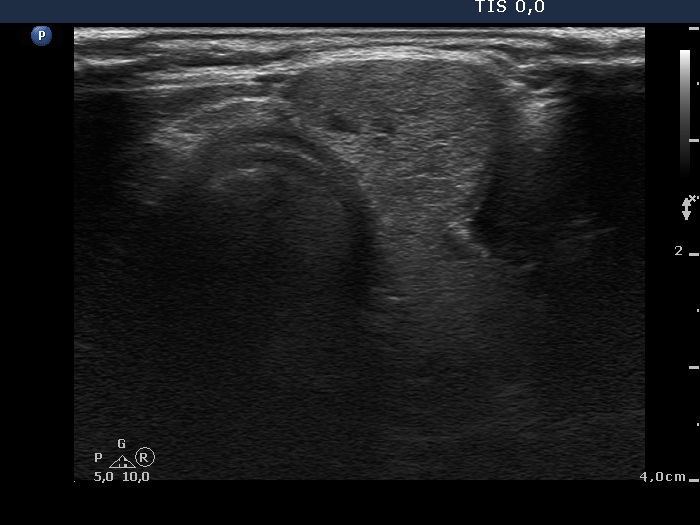

Ultrasonography. The thyroid was echonormal. There were multiple moderately hypoechogenic nodules in the right lobe making the appearance micronodular. There was a relatively larger hyperechogenic nodule in the isthmus. The left lobe contained a hypoechogenic lesion, which presented blurred borders, microcalcifications and an increase intranodular blood flow.